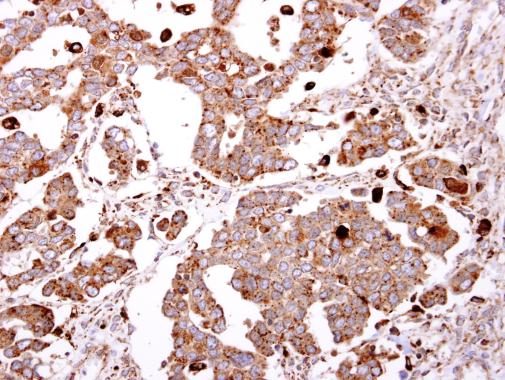

beta-Gal antibody [N2C3] detects beta-Gal protein at cytosol on human ovarian carcinoma by immunohistochemical analysis.

Sample: Paraffin-embedded human ovarian carcinoma.

beta-Gal antibody [N2C3] (GTX104360) dilution: 1:500.

Antigen Retrieval: Trilogy™ (EDTA based, pH 8.0) buffer, 15min